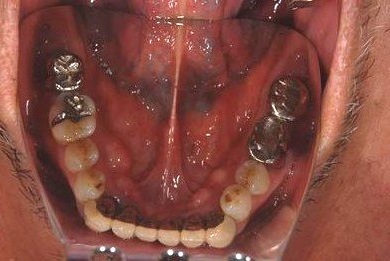

| 性別/年齢 | 男性 / 67歳 | ||||||||||||||||||||||||||||||||

| 治療方針 | サイナスリフト、ソケットリフトによりインプラント治療を可能にする。抜歯と同時にインプラントを埋入し、治療期間を短縮する。 | ||||||||||||||||||||||||||||||||

| 治療内容 | インプラント8本(サイナスリフト、ソケットリフト、GBR)、メタルボンドセラミック8本 | ||||||||||||||||||||||||||||||||

| 治療期間 | 1年5ヶ月 |